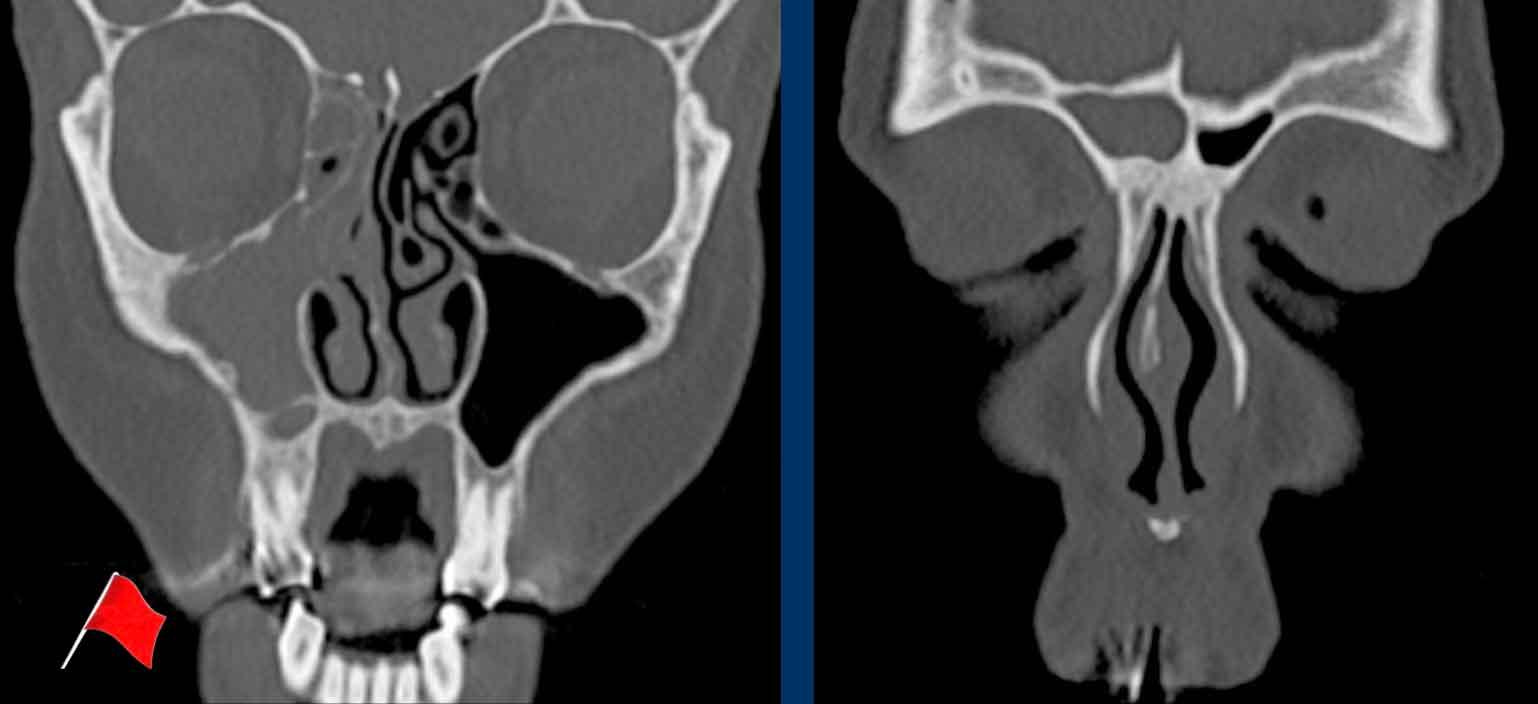

Các hình ảnh này của bệnh nhân nam 47 tuổi, có triệu chứng căng tức vùng trán.

- Tổn thương giãn rộng đẩy nhãn cầu trái sang bên.

- Tổn thương có bờ rõ nét.

- Tổn thương xuất phát từ xoang trán trái.

- Thành trong hốc mắt trái (đầu mũi tên đen) và nền sọ (đầu mũi tên trắng) bị mỏng đi, nhưng không có phá hủy xương.

MRI được thực hiện để xác nhận chẩn đoán nhiều khả năng nhất là nang nhầy…

MRI cho thấy tổn thương giãn rộng chỉ có ngấm thuốc tương phản từ ở vùng viền ngoại vi.

Không có ngấm thuốc bên trong tổn thương.

Điều này xác nhận chẩn đoán nang nhầy.

Nang nhầy là tổn thương dạng nang chứa đầy chất nhầy.

Nang hình thành khi lỗ thông của (một phần) xoang cạnh mũi bị tắc nghẽn.

Dưới đây là thêm các ví dụ về nang nhầy.

- Nang nhầy nhỏ

ở xoang bướm.

Xoang bị lấp đầy hoàn toàn bởi mô mềm (tức là chất nhầy) kèm theo giãn rộng với bờ xương xoang còn nguyên vẹn. - Nang nhầy xoang trán.

Đôi khi, bờ xương bị mỏng đi có thể gây nhầm lẫn với phá hủy xương. Trên các lát cắt CT mỏng, thường có thể nhìn thấy cấu trúc xương còn nguyên vẹn. - Nang nhầy của tế bào xoang sàng trước.

- Nang nhầy xoang bướm phải. Vách liên xoang bướm bị đẩy giãn rộng qua đường giữa.

- Nang nhầy xoang trán.

- Nang nhầy xoang sàng phải với tình trạng mỏng và giãn rộng của lamina papyracea vào hốc mắt cùng bên.